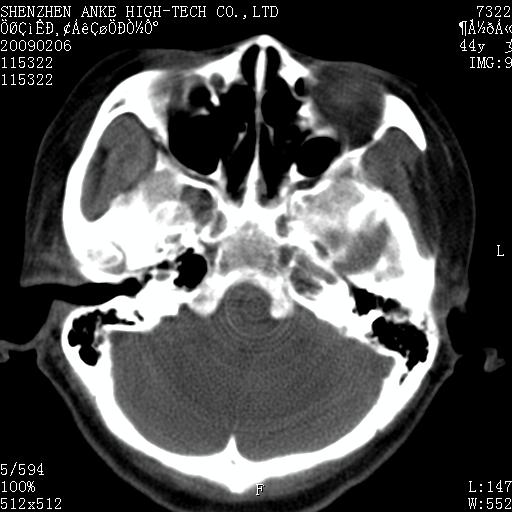

标题: CT17977:女,44岁,右侧颌部包块1年,右侧面瘫2月。 [打印本页]

患者:女,44岁,右侧颌部包块1年,右侧面瘫2月。

考虑右侧腮腺混合瘤可能性大

考虑右侧腮腺混合瘤。

考虑右侧腮腺混合瘤。年轮样伪影考虑机器问题!

考虑右侧腮腺混合瘤;不排除腮腺癌。

右侧腮腺肿瘤,良恶性难定。